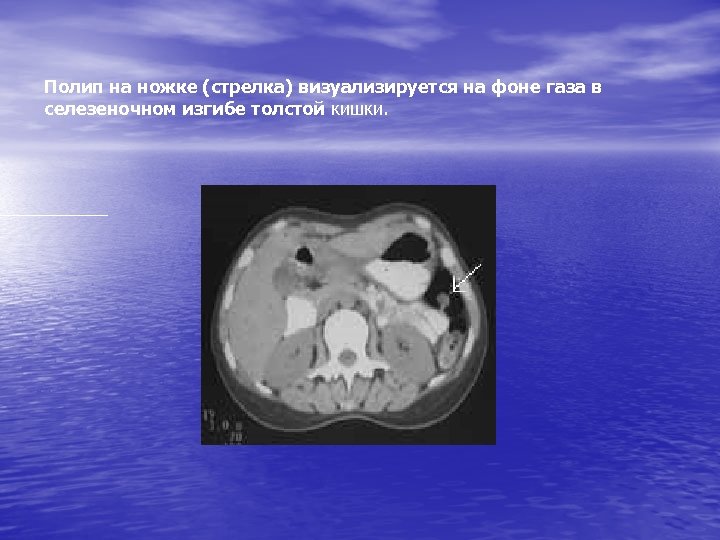

Полип на ножке (стрелка) визуализируется на фоне газа в селезеночном изгибе толстой кишки.